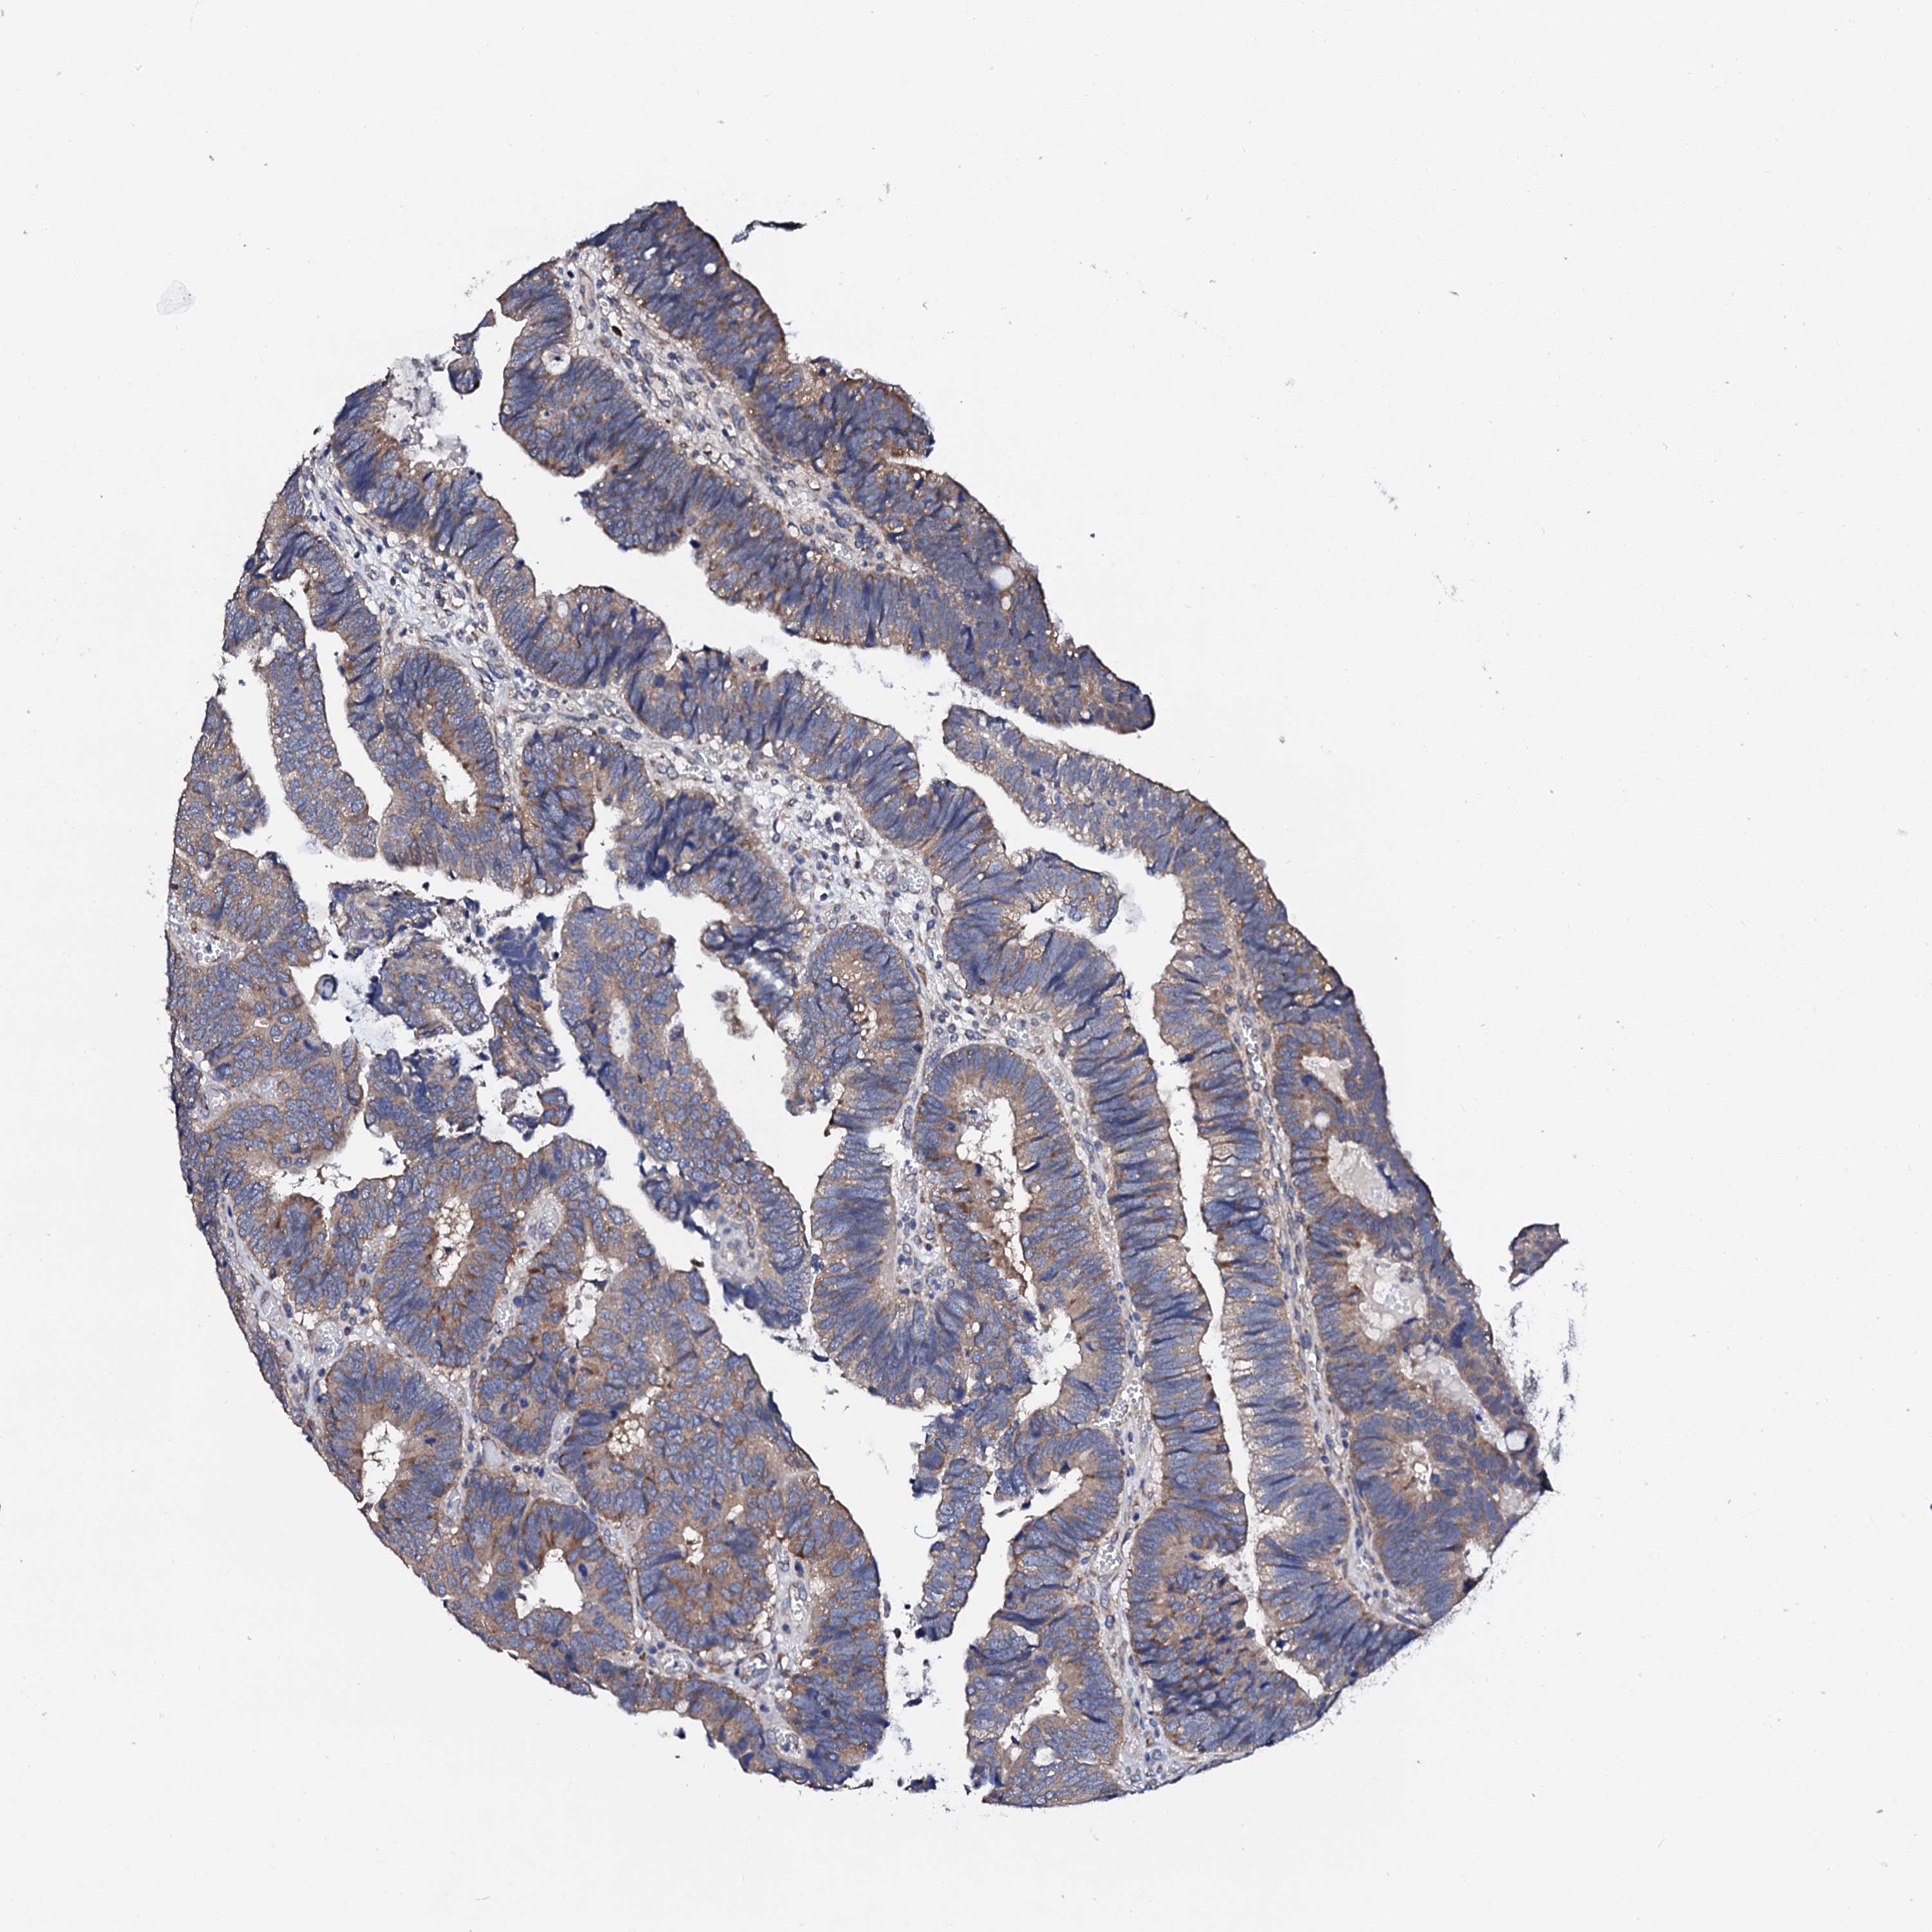

CANCER COLORECTAL CANCER Show tissue menu

Colorectal cancer

Human cancer

Colon adenocarcinoma